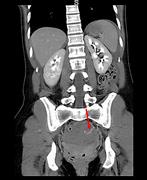

Extensive portal venous gas in a post-operative patient with no identifiable cause

Adam Hussein and Rohit Makhija

Journal of Surgical Case Reports, Volume 2015, Issue 10, October 2015, rjv136, https://doi.org/10.1093/jscr/rjv136